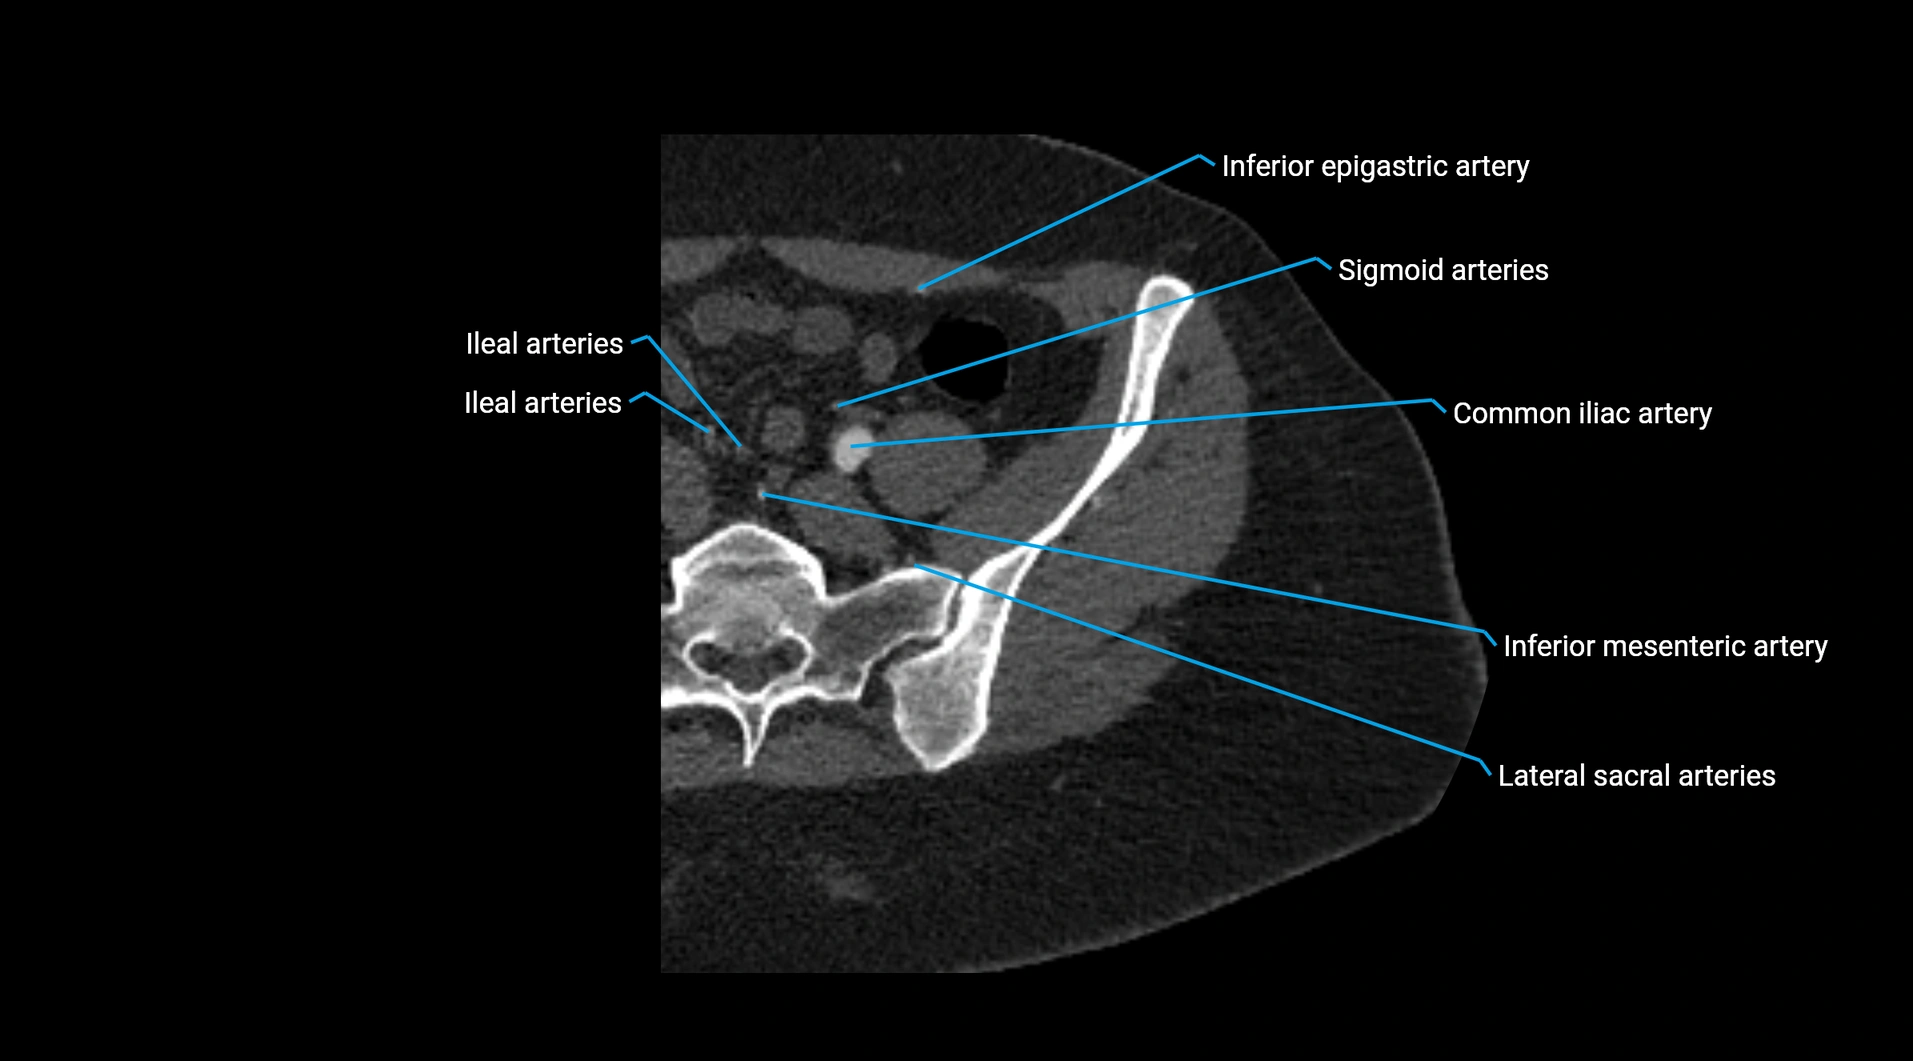

Contrast-enhanced CT (CTA):

• Gold standard for abdominal aortic imaging

• Provides excellent detail of lumen, wall, aneurysm, thrombus, and branch vessels

• Multiplanar and 3D reconstructions help in aneurysm measurement, stent graft planning, and dissection evaluation

• Detects acute rupture, traumatic injury, or occlusion with high sensitivity